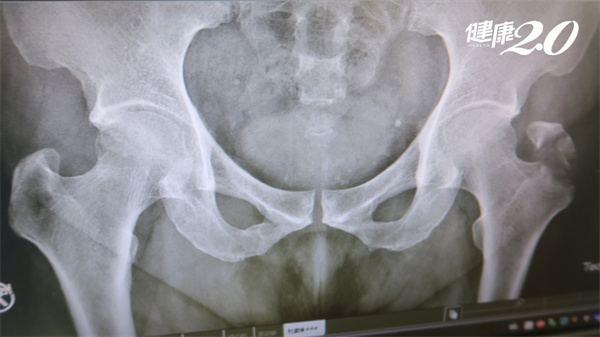

55歲杜先生下樓梯滑倒,送急診後,醫師判斷左髖部骨頭有骨裂,會痛是正常的,有可能會自行癒合,因此患者不以為意,卻又持續疼痛,痛逾1個月轉診後,骨科醫師發現,患者的髖部左股骨大轉子已經位移骨折4公分,經手術後才好轉。醫師提醒,骨裂後續極可能位移骨折,疼痛超過2周一定要持續追蹤!

衛福部彰化醫院骨科醫師洪宗賢表示,杜先生可能原本只是骨裂,但在生活中,髖部位不太可能不去動到,才擴大傷勢為左股骨大轉子位移了4公分,不得不進行復位手術;若不進行復位,未來會變成慢性疼痛,髖骨沒力,走路會極不舒服。

洪宗賢醫師強調,骨裂也稱線性骨折,可能會自然癒合,但更大的可能是惡化成位移骨折,也就是說,骨頭裂縫被拉開,骨頭移動了。從臨床上來看,走動會牽扯到的髖部,從骨裂變成位移骨折的機率大,自然癒合的機率小,相較之下,若是肩膀或胸部肋骨等處的骨裂,活動時比較不會拉扯到,自然癒合的機率就比較大。